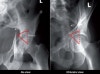

2) Obturator foramen view : anterior column과 posterior wall

3) Iliac wing view : posterior column과 anterior wall

5) Spur sign : 양주 골절의 특징적 소견으로 Obturator foramen view에서 관찰할 수 있습니다.